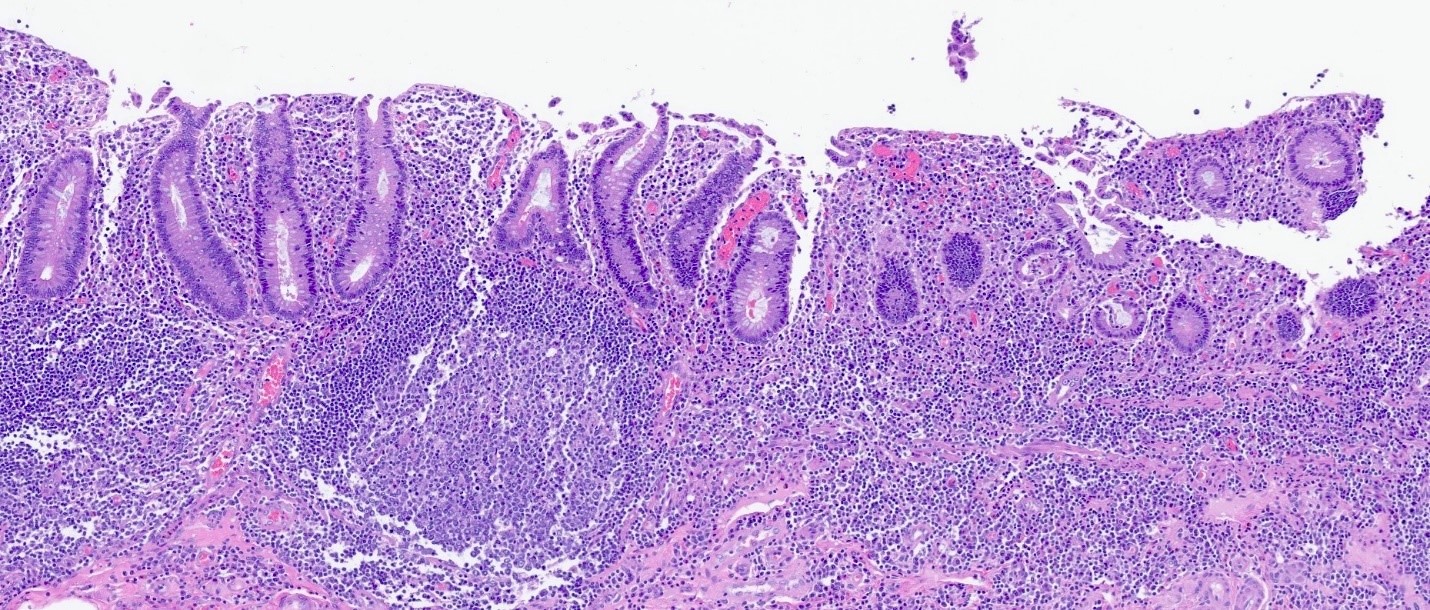

Microscopic (histologic) images

Contributed by Catherine E. Hagen, M.D. and Dustin W. Parsons, M.D.

Prominent lymphoid follicles Prominent lymphoid follicles Prominent lymphoid follicles

Prominent lymphoid follicles

Microscopic (histologic) description

• Lymphoid follicular hyperplasia with germinal centers

• Muscularis mucosa hypertrophy, which is often patchy

• Architectural changes with distortion of crypts, crypt branching and loss of crypts

• Degenerative mucosal surface epithelium with cell exfoliation and pyknotic nuclei

• Loss of goblet cells and mucin

• Mucosal ulceration with granulation tissue

• Varying degrees of inflammation, with features of both activity (neutrophil predominant) and chronicity (lymphoplasmacytic)

• Focal edema

• Pseudopolyps

• Paneth cell metaplasia

• References: Hum Pathol 2022;123:31, World J Gastroenterol 2018;24:1734, Histopathology 1991;19:55